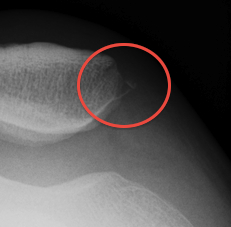

Abnormal / Crossover

- line of floor of trochlea crosses lateral lip of condyle

- indicates trochlea is deficient proximally